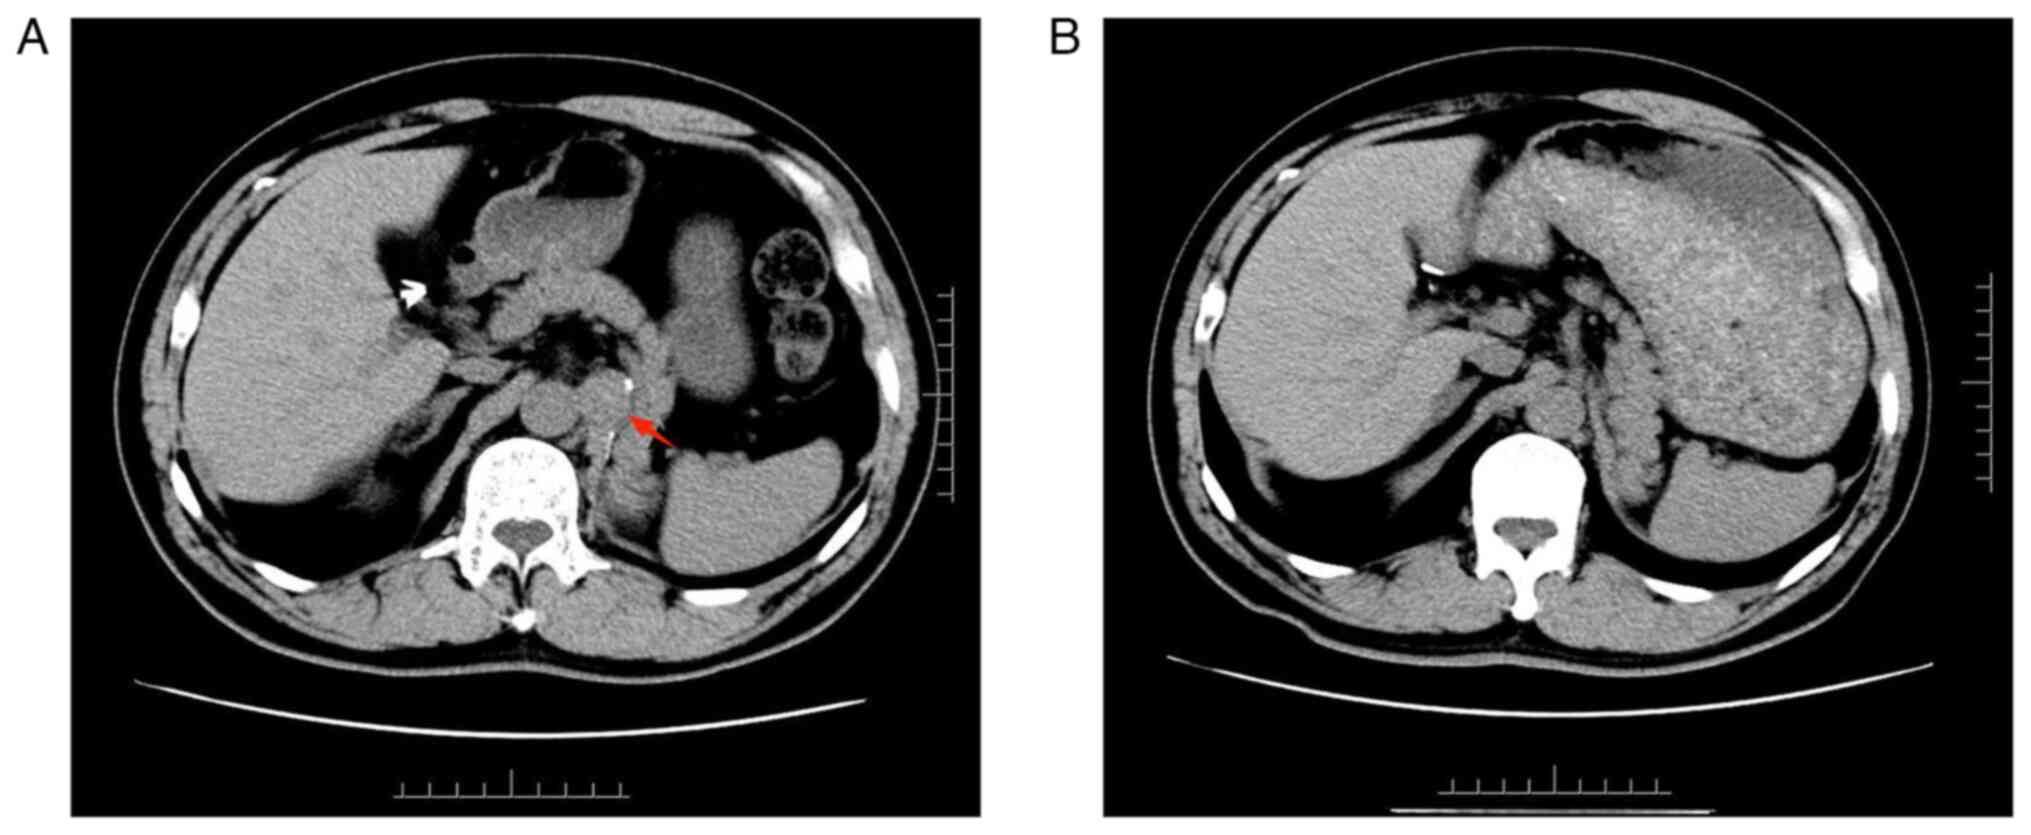

The patient was a 55-year-old male who was admitted to the Thyroid Surgery Department of The Affiliated Hospital of Southwest Medical University (Luzhou, China) in February 2022 due to the presence of thyroid nodules. In April 2018, the patient underwent radical resection of the left kidney for ccRCC at Xinqiao Hospital, Third Military Medical University (Chongqing, China). After the operation, the pathological examination results suggested the following: Renal clear cell carcinoma, pT1aN0M0, the tumor sized ~4.0×4×3.5 cm3, with no lymph node cancer metastases or distant metastasis. Therefore, the patient refused conventional adjuvant therapy after the surgery and underwent regular physical examination follow-up. In November 2021, abdominal computed tomography (CT) revealed para-aortic lymph node carcinoma metastasis (Fig. 1A), positron emission tomography (PET)-CT showed that the patient had a left para-aortic nodule after left nephrectomy and furthermore, glucose metabolism was slightly increased, and the nodule was suspected to be lymph node metastasis (Fig. 2A and B). Bilateral thyroid nodules and increased glucose metabolism were considered to indicate thyroid cancer (Fig. 2C and D), and the patient underwent laparoscopic retroperitoneal mass resection. Postoperative pathological examination suggested lymph node metastasis of ccRCC. Postoperative review via enhanced abdominal CT indicated complete resection of the retroperitoneal metastases (Fig. 1B). In November 2021, thyroid ultrasound Doppler revealed hypoechoic nodules in the left thyroid gland, resembling Chinese-Thyroid Imaging Reporting and Data System (C-TIRADS) 4C (nodule 1: Red arrow) and C-TIRADS 4B (nodule 2: Green arrow) (Fig. 3A). Of note, C-TIRADS is Chinese version of TIRADS suitable for Chinese clinical practice modified based on thyroid ultrasound data in China. The Chinese Medical Association Ultrasound Medical Expert Committee modified the data system by current TIRADS and non-TIRADS risk stratification, combined with the latest literature reported in China and worldwide, keeping in mind the national conditions (9). The cervical lymph node at level VI was enlarged with an abnormal structure, with a maximum size of 0.5×0.3 cm2. Histocytological examination performed according to standard procedures (10) by fine-needle aspiration (FNA) suggested PTC (nodule 1) (Fig. 3B). As the time interval between thyroid surgery and the previous retroperitoneal mass resection was relatively short, contrast-enhanced CT of the head, neck, chest and abdomen was performed prior to thyroid surgery and no obvious evidence of metastasis was found. Therefore, PET-CT was not performed again. However, it was recommended to the patient to repeat the PET-CT for the systemic assessment at a later follow-up visit. Based on the abovementioned examination results, papillary carcinoma of the left thyroid gland was suspected before surgery and surgical resection was performed in February 2022. During surgery, two gray hard masses sized ~0.4×0.3×0.3 cm3 (nodule 1: red arrow) and 1.3×1.3×1.2 cm3 (nodule 2: Green arrow) were found in the left thyroid gland close to the capsule, with an unclear boundary (Fig. 4), and the distance between the two tumors was ~1 cm. Intraoperative frozen section analysis showed that the nodules were neoplastic, with capsule invasion and suspected vascular invasion, and were suggestive of follicular or medullary carcinoma. Accordingly, the nature of the tumor could not be determined as PTC, follicular carcinoma or medullary carcinoma based on FNA and intraoperative frozen section analysis results of the thyroid nodule alone. According to the 2021 Chinese Society of Clinical Oncology differentiated thyroid cancer guidelines (11) and the revised American Thyroid Association guidelines for the diagnosis and treatment of medullary thyroid cancer (12), the patient then underwent total thyroidectomy and bilateral central lymph node dissection. The histopathological examination results were as follows: Left lobe thyroid tumor (two nodules), nodule 1: The nodule composed of partly follicles and partly papillary structures lined by tumor cells with enlarged, crowded and overlapping nuclei; the tumor cells showed nuclear furrows and prominent nucleoli, and certain nuclei had a ground-glass appearance (Fig. 5A); nodule 2: The tumor cells were arranged in nests and sheets, with a large volume, clear cytoplasm, round and centered nuclei and no obvious nucleoli; abundant blood vessels were seen in the background of the tumor (Fig. 5B); follicular adenoma of the right lobe of the thyroid and reactive hyperplasia of bilateral central lymph nodes were observed. Immunohistochemistry (dewaxing of paraffin sections using xylene and descending ethanol 5 min → 100% ethanol 5 min → 90% ethanol 5 min → 80% ethanol 5 min 70% ethanol 5 min → PBS buffer rinse three times, 5 min each time. 2. Antigen repair: EDTA repair solution (PH=9.0), high-pressure repair, and steam was added for 6 min; Citric acid buffer (PH=6.0) was used for repair under high pressure, and steam was added for 3 min. The sample was naturally cooled to room temperature. 3. Further, 3.3% methanol H2O2 was soaked for 10 min to eliminate the endogenous peroxidase activity, and PBS buffer was used to rinse three times (3 min each time). 4. The primary antibody was added and incubated at 37°C for 60 min; followed by washing with PBS three times, each time for 3 min. The secondary antibody (MaxVision™ 2/HRP) was then added and incubates at 37°C for 30 min; followed by washing with PBS three times, each time for 3 min. DAB color development was performed at room temperature for 0.5–1 min; the process was controlled using a microscope, and the sample was washed with tap water to stop color development. 7. Rinsing with running water for 5 min. 8. Re-staining with hematoxylin for 2 min. 9. Further, differentiation was performed using 0.1% diluted hydrochloric acid, and saturated lithium carbonate turned blue. 10. Dehydration, transparency, and sealing: 95% ethanol (l) 1 min → 95% ethanol (l) 5 min → 100% ethanol (l) 5 min → 100% ethanol (II) 5 min → xylene 2 min → neutral gum resin sealing.) revealed the following: Nodule 1: The tumor cell component was immunoreactive to thyroglobulin (TG), thyroid transcription factor-1 (TTF-1), cytokeratin 19 (CK19) and galectin-3 (Fig. 6A-D), but common acute lymphocyte leukemia antigen (CD10) and renal cell carcinoma marker (RCC) staining were negative (data not shown). Nodule 2: The clear cell component showed immunopositivity for CD10, paired box gene 8 (PAX8) and RCC (Fig. 7A-C), but TG and TTF-1 staining were negative (data not shown). In brief, consecutive parallel sections were stained with the following antibodies according to the manufacturers' recommendations: TG (cat. no. MAB-0797), TTF-1 (mouse anti-human mAb; cat. no. MAB-0677; Maixin Fuzhou), CK19 (mouse anti-human mAb; cat. no. MAB-0829), galectin-3 (cat. no. MAB-0835; Maixin Fuzhou), CD10 (cat. no.MAB-0668), PAX8 (cat. no. MAB-0837; Maixin Fuzhou), RCC (all mouse anti-human mAb; cat. no. MAB-0309; all Maixin Fuzhou). The secondary antibody was MaxVision™ 2 plus polymer HRP (mouse/rabbit) IHC Kit (cat. no. KIT-5930; Maixin Fuzhou). However, the absence of quantitative results for these experiments is a limitation of the present study. On postoperative day 1, the parathyroid hormone level was 5.14 pg/ml (reference range, 8.7–79.6 pg/ml) and the blood calcium concentration was 1.98 mmol/l (reference range, 2.11–2.52 mmol/l). The patient presented with fingertip and perioral numbness, which may be caused by transient hypocalcemia resulting from impaired parathyroid blood supply. Treatment with calcium supplementation was provided, and the parathyroid hormone and blood calcium concentration were reexamined on postoperative day 3. The parathyroid hormone levels were 10.4 pg/ml and the blood calcium concentration was 2.36 mmol/l. The patient did not show any hypocalcemia again. Levothyroxine (100 mg qd) was administered on postoperative day 2. Following thyroid surgery, multidisciplinary consultations were acquired from the Departments of Urology, Oncology and Thyroid Surgery, and other disciplines. This patient had undergone surgical resection and was treated with sunitinib (50 mg qd) for 2 cycles (taking sunitinib for four weeks per cycle followed by a two-week interval). The patient was followed up for 14 months and followed a good diet and having a good sleep, and normal thyroid function and no new metastasis was observed. Hereafter, the patient will be followed up every 3 months and the results will be reported.

Figure 1.

Abdominal CT. (A) Abdominal CT in November 2021 revealed para-aortic lymph node carcinoma metastasis (red arrow). (B) Postoperative review via enhanced abdominal CT in February 2022 indicated complete resection of retroperitoneal metastases. CT, computed tomography.